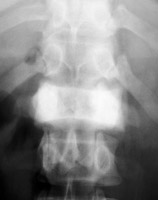

A uniformly white vertebra with no abnormality of its contour or adjacent disks. The vertebra stands out against the adjacent normal, or darker, vertebral bodies. While the list of possible etiologies of ivory vertebrae is extensive, the most common causes of ivory vertebrae are typically metastatic disease, and Paget’s. A-B. Metastatic breast cancer. C-D. Paget's disease.

Lateral lumbar spine - Click on the image for a larger versionAAP lumbar spine - Click on the image for a larger versionBIvory Vertebra - Click on the image for a larger versionCIvory Vertebra - Click on the image for a larger versionD